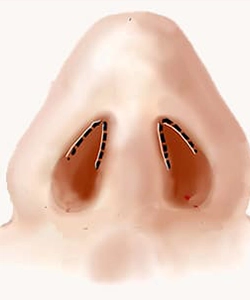

اصلاح افتادگی یا پهنی نوک بینی، باریکسازی متعادل

تقارن پرههای بینی و بهبود زاویه بینی و لب بالا

ترمیم دریچههای داخلی/خارجی بینی برای جلوگیری از کلاپس هنگام دم

برشها داخل بینی انجام میشود؛ هیچ برش خارجی روی کلوملا دیده نمیشود.